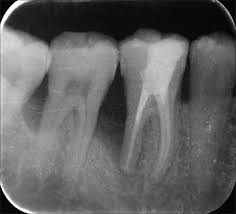

Calcificación Pulpar

La calcificación pulpar es la formación de depósitos de calcio dentro de la pulpa dental, que puede dificultar el tratamiento de conducto.

Los pacientes generalmente no tienen síntomas, pero pueden experimentar sensibilidad.

El tratamiento incluye la eliminación de los depósitos durante el tratamiento de conducto. Es importante tratarlo para evitar complicaciones durante el procedimiento.